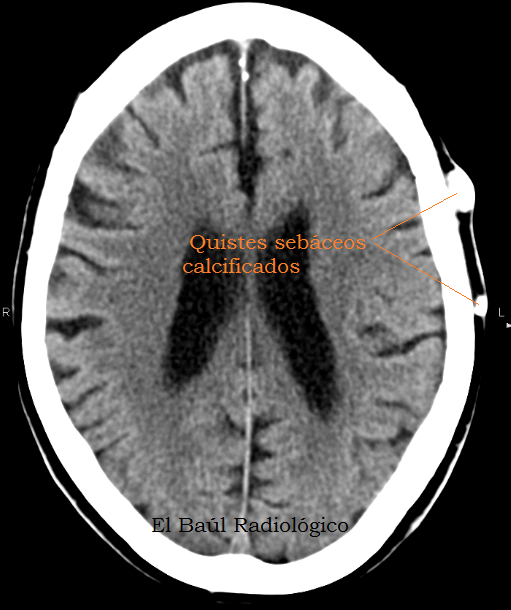

Uno de los hallazgos más frecuentes en las exploraciones de Tomografía Computarizada o Tomografía por Resonancia Magnética (TRM) craneoencefálicas son los quistes sebáceos del cuero cabelludo. Algunos los confunden con osteomas, pero son cosas completamente distintas y su repercusión patológica también. Los quistes sebáceos pueden formarse en la piel de cualquier parte del cuerpo. Son nódulos duros, desplazables porque no están adheridos a estructuras profundas. Se originan en la dermis, en la base de un folículo piloso. Rodeados por una cápsula, contienen restos de tejidos cutáneos, conglomerados de queratina y calcificaciones grumosas que les confieren el aspecto hiperdenso en las imágenes de Tomografía Computarizada (Figura 1). Son de morfologia redondeada, están en contacto con el hueso, pero no dependen de él como los osteomas que se originan en el hueso compacto cortical y tienen una base de inserción plana. Los quistes sebáceos son siempre benignos y no se extirpan, salvo por problemas estéticos.

FIGURA 2) Imagen axial de TC craneo-encefálica en la que se observan dos quistes sebáceos calcificados del cuero cabelludo. Es un hallazgo muy frecuente y no deben ser etiquetados de osteomas.

(AxialCTimagein which we can appreciate, in the scalp, twocalcifiedsebaceous cysts. It is avery common findingand they should not beconfusedwithosteomas)